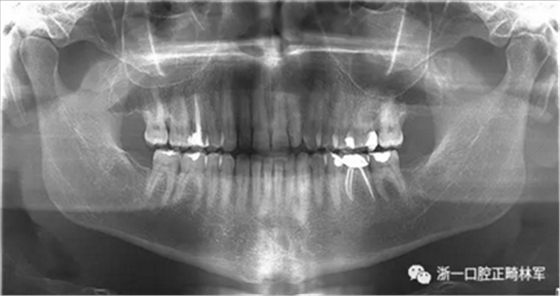

在最初的正畸咨询期间,拍摄了口内和口外照片连同一张全景片(图2),一张侧位头影片(图3)和正畸研究模型的海藻酸盐印模。

一位寻求改善微笑面容的43岁荷兰阿尔梅勒男子通过其全科牙医的介绍来到一家正畸医生的私人诊所,以纠正其错合畸形并在上颌前牙区域放置6个贴面。他属于牙形I类错合畸形,轻度骨性III类,覆合和覆盖减少以及前牙区存在间隙(图1)。